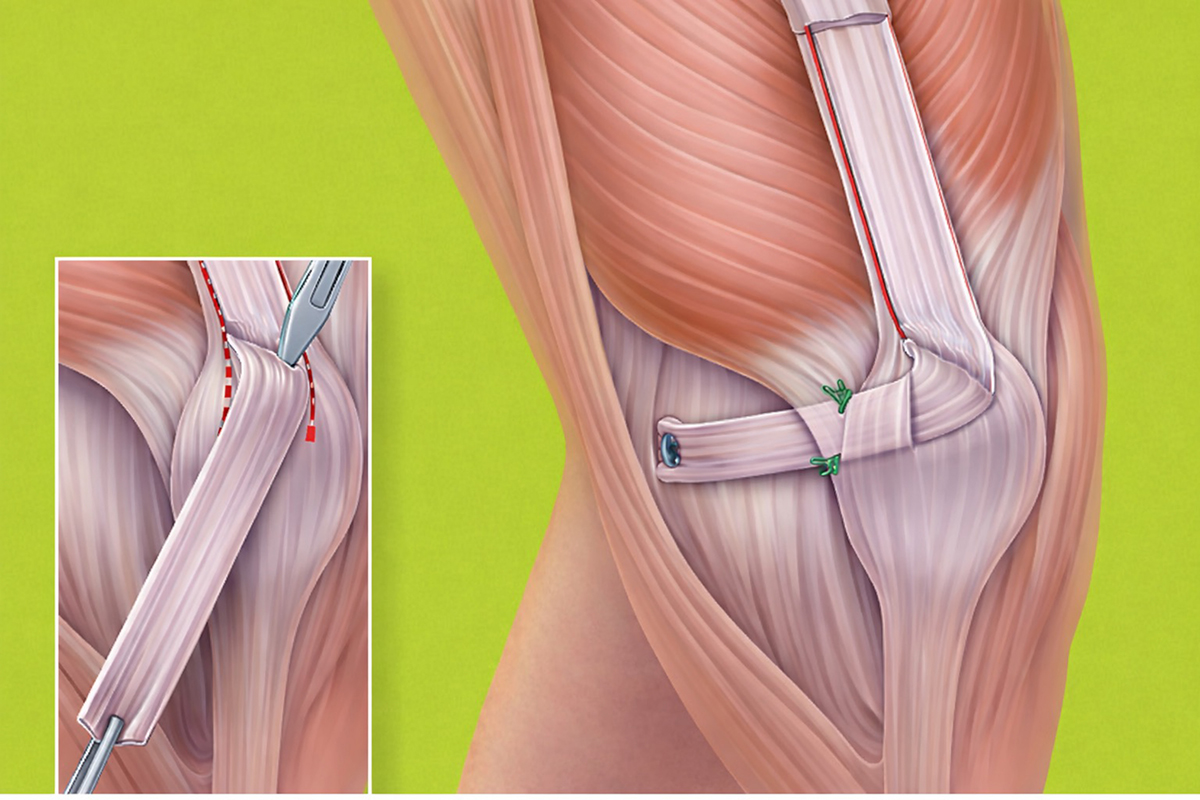

1. Rekonstruktion des Bandapparats

Basisverfahren bei wiederholter Instabilität und in ausgewählten Erstluxationen. Es stellt die wichtigste innenseitige Weichteilstabilisierung wieder her.

2. Versetzung des Patellasehnenansatzes

Indiziert bei deutlicher Lateralisierung und/oder Patellahochstand, ggf. auch zur Lastumverteilung bei Knorpelschäden. Das Ziel ist eine günstigere Zuglinie und frühere, stabilere Führung der Patella.